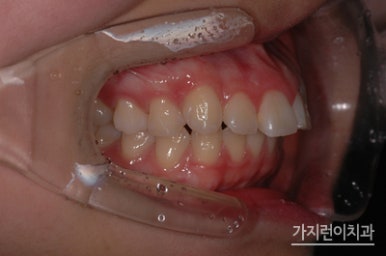

환자 분의 거미스마일과 돌출입 증상은 위 사진과 같았습니다. 치아 돌출은 물론이고 잇몸이 과도하게 나타나는 증상 때문에 스트레스를 상당히 많이 받으셨는데요. 앞으로 나온 부분을 뒤로 집어넣기 위해 상하악 양쪽의 어금니를 발치하였고

미니스크류를 식립해 상악 전치의 후방과 함입 시키는 과정을 진행했습니다. 여기서 말하는 함입과정은 상악 전치를 위로 들어올리는 과정을 말하는데요. 충분한 힘을 주기 위해 미니스크류를 식립했으며

하악에도 미니스크류를 식립해 상하악 전치가 동시에 후방으로 들어갈 수 있도록 조치를 취했습니다. 이런 교정의 과정 끝에 1년 8개월이라는 시간이 소요 되었는데요. 하지만 수술적인 방법 없이 교정만으로도 돌출입교정과 거미스마일 치아교정을 성공적으로 마쳤기에 환자분의 만족도가 높았던 과정이었습니다.